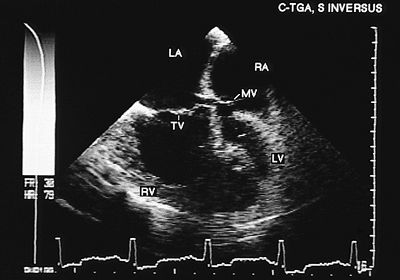

Congenitally Corrected Transposition

In congenitally corrected transposition, both the A–V and the V–A connections are discordant. Associated defects, especially ventricular septal defect, either isolated or with pulmonary valve stenosis, are common, occurring in 70% to 90% of cases. Cardiac malpositions also are commonly associated and can make it difficult to obtain satisfactory transthoracic recordings. The study of these patients should include transesophageal and transgastric recordings, and the main findings are discussed in the following paragraphs (4).

A–V discordance is established by identifying atrial situs and the position of the ventricles using the criteria discussed at the beginning of the chapter. The most reliable way of identifying the atria is through the morphology of the atrial appendages. The principal signs used for the identification of the ventricles are the different levels of implantation of the mitral and tricuspid septal leaflets (when ventricular septal defect is absent) and insertion of the tricuspid chordae tendineae in the interventricular septum. In addition, the ventricular morphology evident in the four-chamber image facilitates recognition—the right ventricular chamber has a triangular shape and the left ventricular chamber an ellipsoid form. These characteristics are independent of the ventricular spatial relationship.

In V–A discordance, identification of the great arteries is based on the bifurcation of the pulmonary artery. The parallel positions of the two vessels can be observed with monoplanar recordings taken at the level of the semilunar valves. When situs is solitus, the aorta is anterior and to the left and the main pulmonary artery posterior and to the right (Fig. 8.2.48). In situs inversus the aorta is anterior but to the right of the main pulmonary artery.

Direct visualization of the connection of the ventricles to the great vessels is facilitated by the use of biplanar transducers. In images in the longitudinal plane it is possible to visualize the connection of the posterior vessel (pulmonary artery) with the left ventricle, to corroborate mitral-pulmonary continuity and to demonstrate the connection between the anterior outflow tract (right ventricular) and the aorta.

It is possible to identify cardiac position from the transesophageal four-chamber image. The apex of the ventricles points to the left in levocardia, to the right in dextrocardia, and toward the midline in mesocardia. Moreover, the subpulmonary outflow tract of the left ventricle is deeply wedged between the mitral and tricuspid valves, which generates malalignment of the atrial and ventricular septum and prominent anterior recess in the morphologically left ventricle.

Transesophageal study is superior to the transthoracic study for visualizing the frequently associated ventricular septal defect. The defect is usually a wide perimembranous type in subpulmonary position. It can be visualized directly in transverse or longitudinal planes.